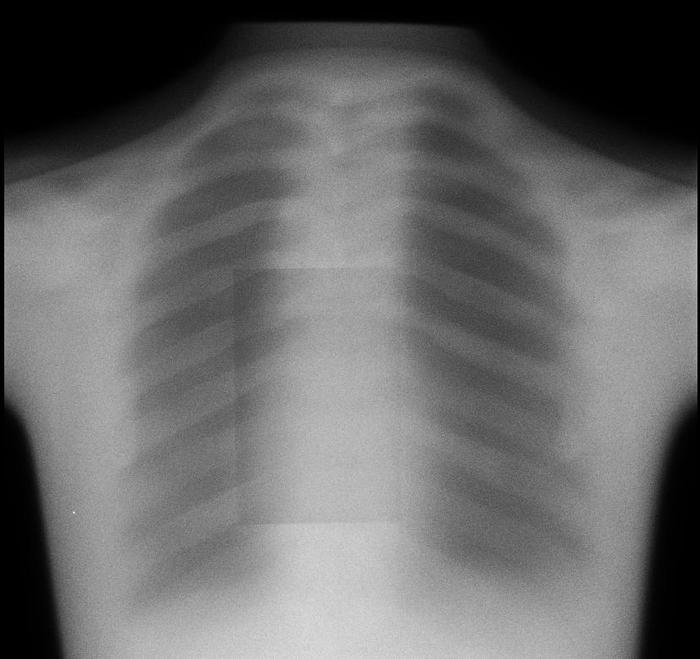

Problem

Solution

For both the lateral and the AP views, there are two separate sources of motion that could contribute to differences between the “pre” and “post” images: movement of the patient and the ovement of the spine and/or screws. The camera itself has preset positions for both views, with millimeter-level noise between separate images that can be effectively ignored. As the movements of the patient are extraneous, they introduce noise that makes it difficult to evaluate patient progress and diagnose any potential issues (e.g. pseudarthrosis) that may cause major health risks. As a result, a patient that may come in after their operation to diagnose why they haven’t seen the expected improvement may require additional x-rays which delay the process, which could result in any medical conditions worsening or potentially another operation being required.

We will create an algorithm enabling users to upload both the “pre” and “post” images, realign/manipulate them, and eliminate noise induced by movement of the patient. By doing so, the lab will be able to make more accurate diagnoses and prognoses of their patients. Having specific, quantitative data on the relative positions and movements of screws and vertebral bodies of interest would help patients to make the best of their own and the lab’s time and diagnose any complications earlier for better health and less cost to the patient.